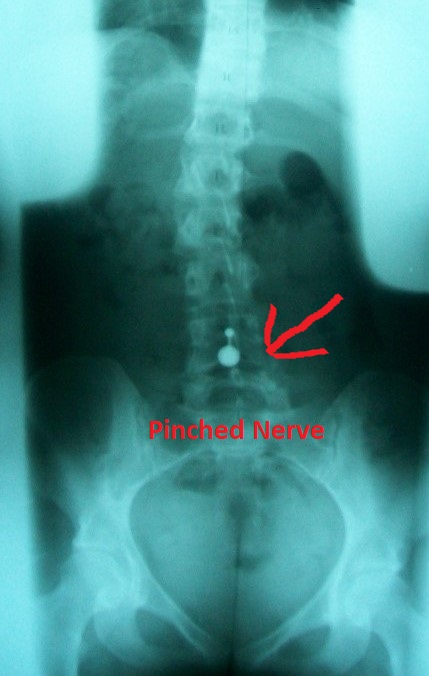

37+ Lower Back Pain Pills Images. Low back pain (lbp) or lumbago is a common disorder involving the muscles, nerves, and bones of the back. Many cases of back pain that occurs on the lower right side (or anywhere in the back) can be prevented.

Back pain can result from injury, disease, or simply aging. (natural news) forget the pill, a massage is the better option for that kink in your back. Diarrhea and lower back pain are common and may be unrelated.

Have had surgery on your spine. While most back twinges go away on their own after a few days, many. Learn more, including what treatments may help with your condition. Diarrhea and lower back pain are common and may be unrelated.